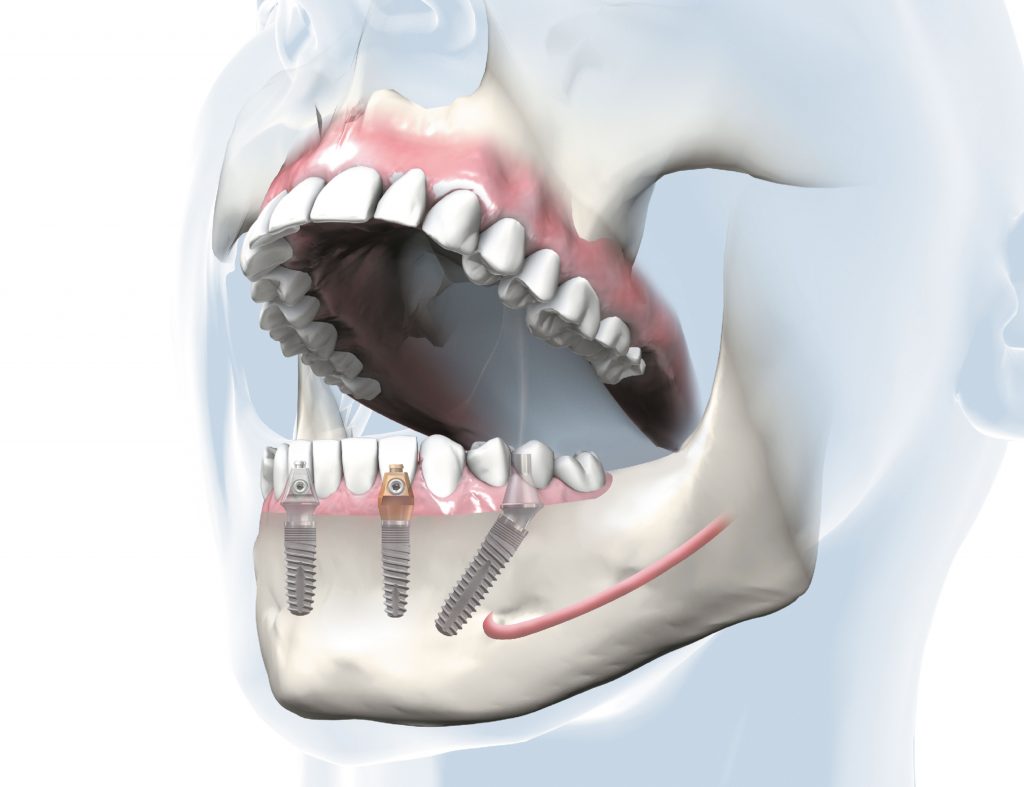

Mit dem Behandlungskonzept "SKY® fast & fixed" können feste Zähne ohne aufwendigen Knochenaufbau innerhalb von nur 24 Stunden im Unter- oder Oberkiefer eingesetzt werden. Dabei werden 4 oder 6 Implantate in den Kieferknochen platziert und der Brückenkörper sicher aufgeschraubt. Im Gegensatz zu herkömmlichen Methoden, die bis zu neun Monate dauern können, reduziert "SKY® fast & fixed" die Behandlungszeit auf nur 24 Stunden.

Darstellung Behandlungskonzept SKY fast & fixed im Unterkiefer